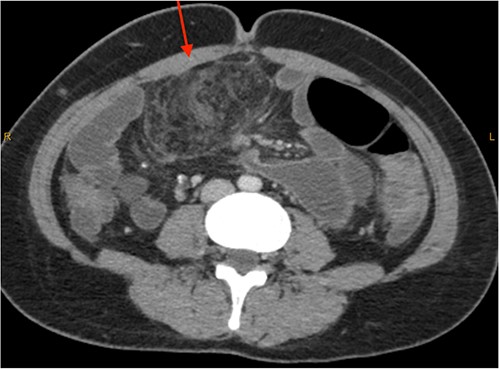

On review of imaging, we noted a CT scan from 2019 which showed swirling and stranding of omentum/mesenteric fat inferior to hepatic flexure (CC 1.8 cm, TV 2.6 cm), with suspicion of internal herniation of the omental/mesenteric fat leading to infarction (Figs 1 and 3). Management of this was unclear as this was at a private hospital in metropolitan Western Australia. A repeat CT scan during her current presentation revealed similar swirling of omentum/mesenteric fat, but with interval increase in size (CC 5.5 cm, TV 7.6 cm). There was associated small bowel dilatation and wall thickening and enhancement with no focal transition point (Figs 2 and 4).

Second, omental torsion is rarely managed conservatively with surveillance imaging. Hence, it is rare that we have CT imaging showing the progression of omental torsion over 4 years, noting the markedly increased dimensions and characteristic mesenteric swirling.